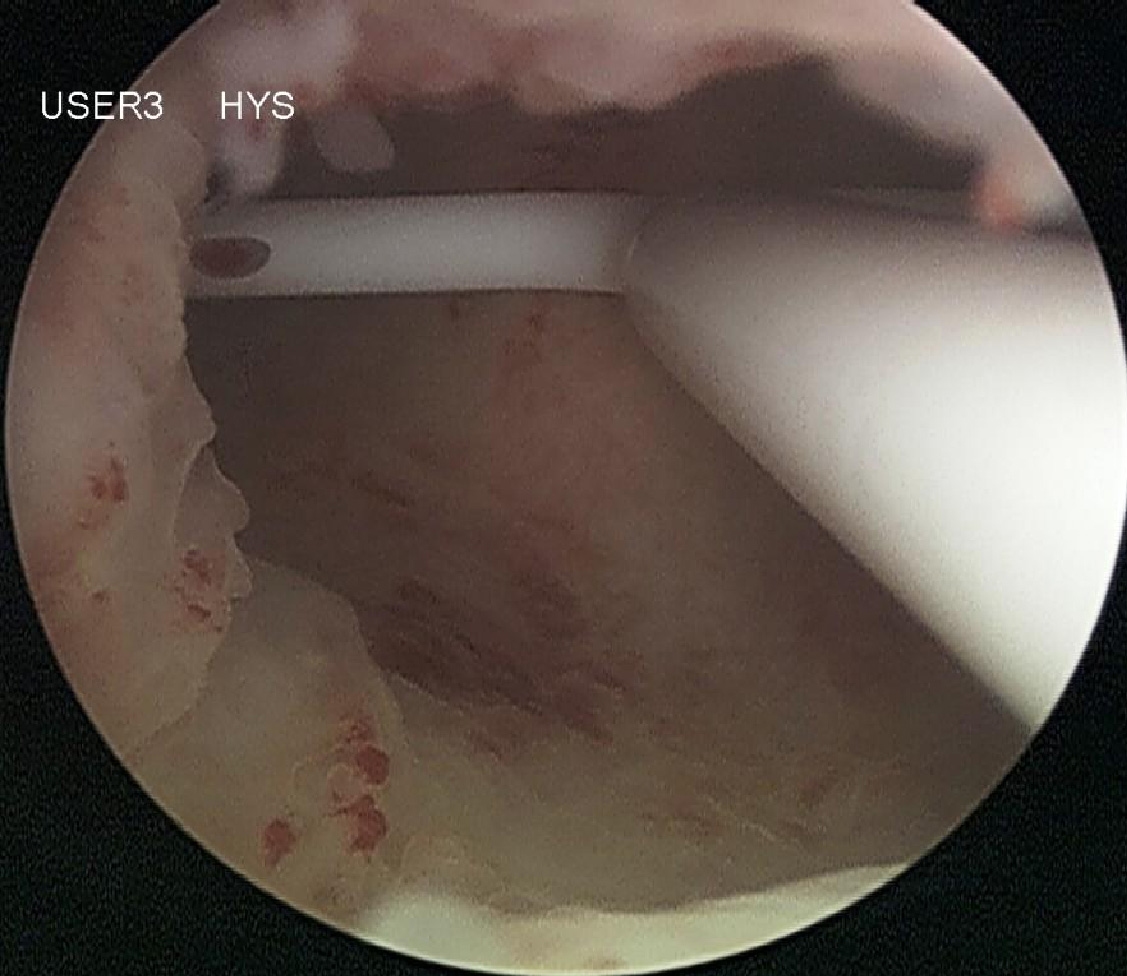

Die Totale Laparoskopische Hysterektomie (TLH)

Im Rahmen dieser Operation wird sowohl der obere Anteil der Gebärmutter, der sogenannte Gebärmutterkörper (Corpus uteri), als auch der Gebärmutterhals (Cervix uteri) entfernt. Die Gebärmutter (Uterus) wird in diesem Zusammenhang von der Scheide getrennt. Auch diese Operation wird komplett per Bauchspiegelung durchgeführt. Die totale laparoskopische Hysterektomie (TLH) birgt im Vergleich zur laparoskopischen suprazervikalen Hysterektomie (LASH) keine wesentlichen zusätzlichen Operationsrisiken. Die Heilung des Beckenbodens und der Scheide erfordert jedoch eine längere und konsequente Schonung. Regelmäßige gynäkologische Kontrolluntersuchungen sind auch nach der Operationsmethode wichtig.

Indikation

Wenn durch die gynäkologischen Vorsorgeuntersuchungen oder im Falle vorangegangener Operationen am Gebärmutterhals (Konisation) eine Veränderung des Gebärmutterhalses diagnostiziert wurde (z. B. Portiodysplasie), sollte im Rahmen der Hysterektomie auch der Gebärmutterhals entfernt werden. Eine komplette operative Entfernung des Uterus kommt auch dann in Frage, wenn dieses dem speziellen Wunsch der Patientin entspricht - beispielsweise aus Angst vor späteren Erkrankungen der Cervix. Da die Entfernung des Gebärmutterhalses eventuell nachteilige Effekte auf Scheide, Blase, Darm und die Sexualfunktion haben kann, sollte die Entscheidung individuell erfolgen.

Klinikaufenthalt und Erholungsphase

Die totale laparoskopische Hysterektomie wird von uns nicht ambulant durchgeführt. Ihr Klinikaufenthalt beträgt zwei bis drei Tage, abhängig von der Operationsdauer und Ihrem allgemeinen gesundheitlichen Zustand. Da bei dieser Operation auch der Gebärmutterhals entfernt wird, sollte die Beckenbodenmuskulatur bis zur kompletten Abheilung geschont werden. Wir empfehlen Ihnen eine Erholungsphase von durchschnittlich sechs Wochen. Die genaue Dauer kann individuell variieren und wird im Rahmen der Kontrolluntersuchungen von Ihrer Gynäkologin bzw. Ihrem Gynäkologen bestimmt. Das Heben schwerer Gewichte sollte zur Vermeidung einer Senkung des Beckenbodens generell vermieden werden.